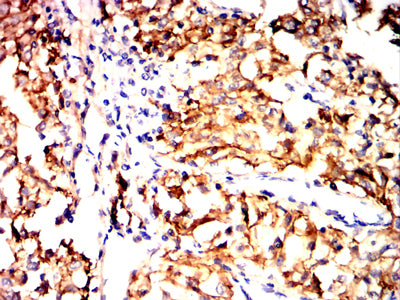

Immunohistochemical analysis of paraffin-embedded human endometrial cancer tissues using SCARB1 mouse mAb with DAB staining.

Immunohistochemical analysis of paraffin-embedded human kidney cancer tissues using SCARB1 mouse mAb with DAB staining.